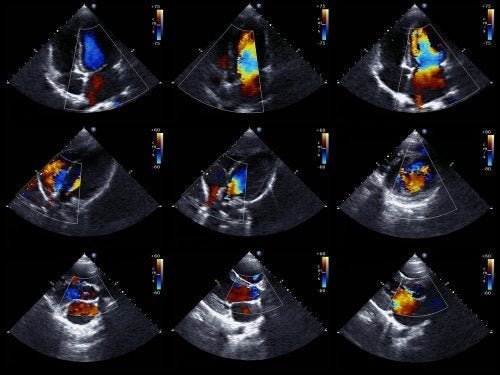

Os médicos geralmente conseguem diagnosticar essa anomalia antes que o bebê nasça. Para isso, eles usam um ecocardiograma fetal. Essa técnica usa ondas sonoras para criar uma imagem do coração em movimento.

Graças a isso, você pode ver a aparência do coração e examinar seu funcionamento quando eles ainda estão no útero. Com as informações obtidas, os médicos programam como tratar o bebê imediatamente após o nascimento.